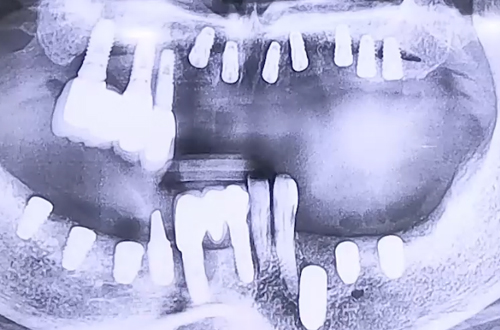

전반적인 임플란트 치료 사례

기존에 다른 치과에서 임플란트 치료를 하다 중단이 되고 시간이 흐르며

임플란트 주변으로 염증이 생기고 나머지 치아들 상태도 안 좋아진 상태로 내원하셨던 환자분이십니다.

환자분은 오른쪽 위 어금니에 기존 임플란트가 되어 있고 오른쪽 아래 어금니는 없으셨고,

왼쪽 아래는 임플란트가 중단되어 보철이 씌워지지 않은 상태이고 앞니와 왼쪽 위 어금니는 치아가 없어

좌우 어느 쪽으로도 음식을 드시기 힘든 상태이셨는데요.

임플란트가 굳고 완성되는 시간은 상대적으로 뼈가 단단한 아랫니가 더 빠르므로,

오른쪽 아래 임플란트를 먼저 진행하여 음식을 조금 더 편하게 드실 수 있도록 해드린 뒤

나머지 치아들의 임플란트를 진행하는 것으로 치료 계획을 잡았습니다.

CT 촬영으로 정확한 신경 위치를 점검하고 안전하게 전체적으로 임플란트를 심어드렸으며

임플란트가 굳는 기간을 기다린 뒤 순차적으로 보철을 완성하며 진행해 드릴 예정입니다. ^^